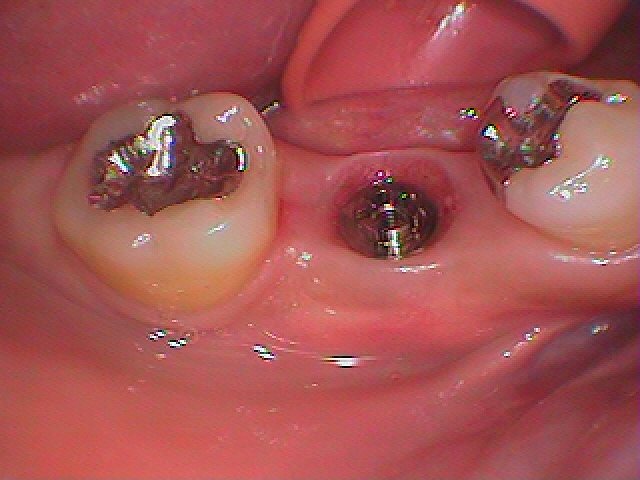

インプラント埋入後2か月になります

抜歯即時インプラント埋入のため抜歯してから2か月ということになります

このように傷がいえています

きれいに治ってきています

口蓋側寄りにしっかりと5㎜の11,5㎜というインプラントを埋入

しています